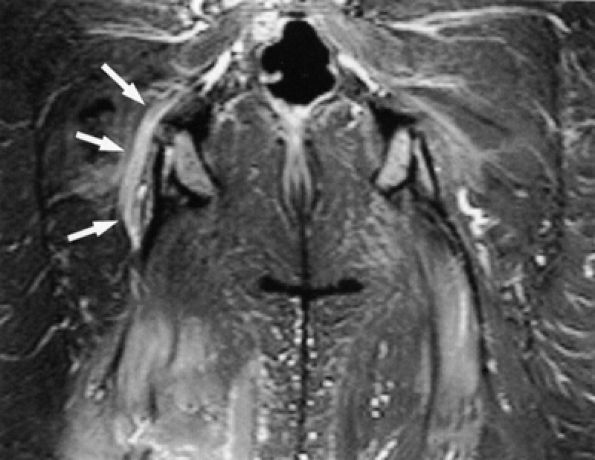

FIGURE 6.14 ● Plexiform neurofibromatosis. (A) Coronal T2-weighted fat-suppressed image depicting fusiform enlargement and increased signal of the right (arrows) and left (arrowheads) sciatic nerves. (B) Axial T2-weighted fat-suppressed image demonstrating the “bag of worms” appearance of the right sciatic nerve (black arrow). Note an intramuscular neurofibroma in the rectus femoris muscle (white arrow).

|